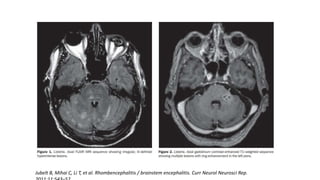

• Increased T2 and FLAIR signal in medulla,

cerebellum and upper cervical cord.

EBV Rhombencephalitis:

• The mean age around 20 years (range, 19–44

years)

• Clinical manifestations fever (75%), ataxia

(100%), and an altered level of consciousness

(50%).

• MRI 50% of the damage was infratentorial .

The mean CSF cell count 25 cells/mm3

(range, 8–55) with 100% lymphocytes.

• Treatment intravenous acyclovir.